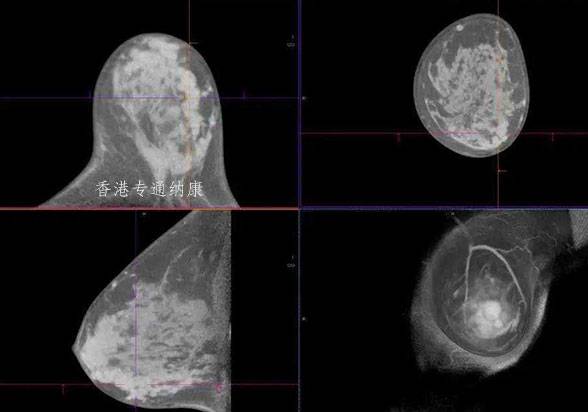

由阿斯利康和日本第一三共联合开发和商业化的全球首个针对HER2低表达转移性乳腺癌患者的靶向疗法Enhertu(简称T-DXd)已在美国获批,用于治疗不可切除或转移性HER2低表达乳腺癌成人患者。

T-DXd是一款独特设计靶向HER2的抗体偶联药物 (ADC)。此次美国食品和药物监督管理局(FDA)的批准是基于DESTINY-Breast04 III期试验的结果,DESTINY-Breast04 是一项全球性、随机、开放标签、注册 III 期试验。凭借在 DESTINY-Breast04 试验中显示的突破性生存获益,这一里程碑证实了靶向HER2低水平表达在治疗转移性乳腺癌中的重要性。